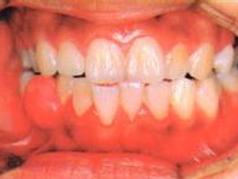

早期患牙有輕度疼痛,此時患牙咬緊,疼痛可以暫時緩解,隨炎症加重,患者齒伸長,有浮出感,輕叩患牙即疼痛。根尖周炎時疼痛為自發性、持續性癌,且範圍局限,患者能明確指出患牙。 如果急性根尖周炎沒有得到治療,炎症繼續發展,形成急性根尖膿腫,則疼痛加劇,叩痛明顯,且有持續性跳痛。膿液擴散至骨膜下,疼痛、腫脹均很明顯,膿液一旦穿破骨膜達到黏膜下,由於壓力減弱,黏膜下組織疏鬆,疼痛比以前減輕。